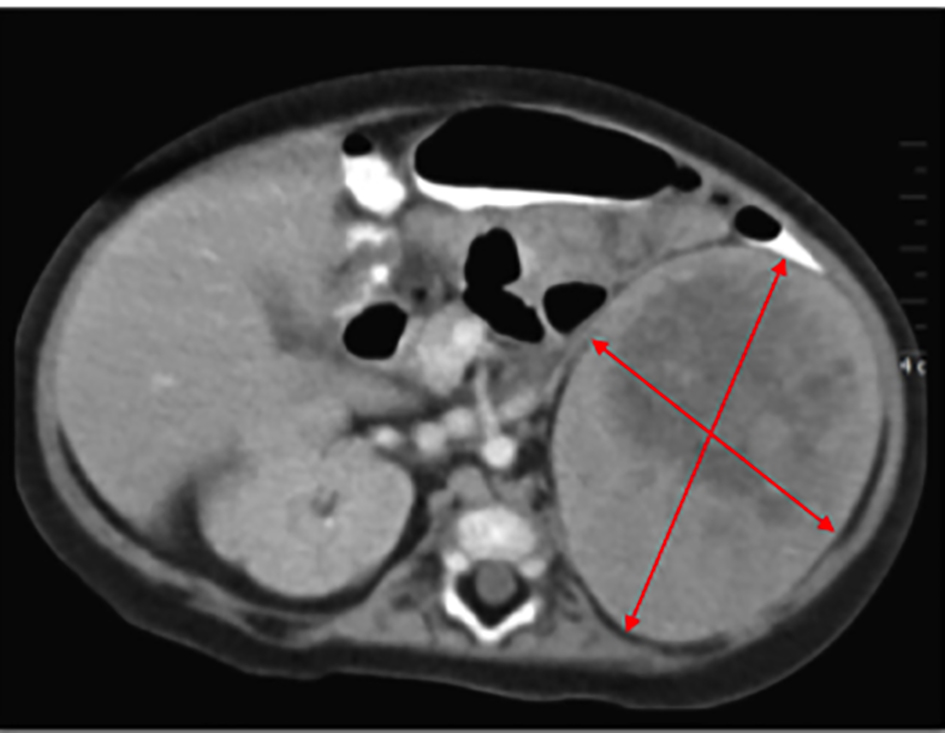

While being treated in the hospital for pneumonia, an evaluation was launched to delineate the etiology of the excessive weight gain, growth arrest, hypotonia and the abdominal mass. Laboratory evaluation revealed consistently elevated serum cortisol levels, irrespective of the time of the day with values of 73.0 μg/dL at 5:08 am and 68.6 μg/dL at 12:50 pm (normal range 4 - 22 μg/dL). Serum adrenocorticotropic hormone (ACTH) was suppressed at 7 pg/mL, at 5:16 am (normal range 0 - 60 pg/mL), suggestive of a primary adrenal cortisol hypersecretion. Dehydroepiandrosterone sulfate (DHEA-S) was mildly elevated at 115 μg/dL (normal range 16 - 96 μg/dL), but clinical features of hyperandrogenism were absent. The aldosterone level was normal at 23 ng/dL with a slightly elevated renin of 43.51 ng/mL/h. There was a slight increase in urine vanillylmandelic acid (VMA) and metanephrines, excluding a pheochromocytoma. An ultrasound demonstrated a 6.8 × 7.7 cm size solid mass at the upper pole of left kidney. A subsequent computerized tomography scan confirmed a large left-sided soft tissue mass with internal necrosis and a well-defined capsule abutting the left kidney with non-visualization of the left adrenal gland (Fig. 2). Henceforth, presumptive diagnosis of a functional cortisol producing adrenal tumor was made.

![]() Click for large image | Figure 2. CT scan reports 6.8 × 7.7 cm size mass at the upper pole of left kidney. |